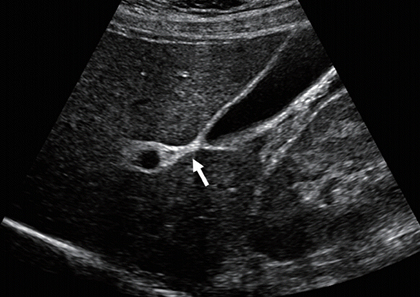

• 담낭 질환 초음파 진단 검사01

• 초음파 검사

• 담낭 질환 진단에 가장 기본적인 검사입니다. 초음파를 통해 담낭 벽의 두께, 담석 유무, 담낭 주위의 액체 고임 등을 확인할 수 있습니다. 특히 금식 후 검사를 통해 더욱 정확한 진단이 가능합니다.